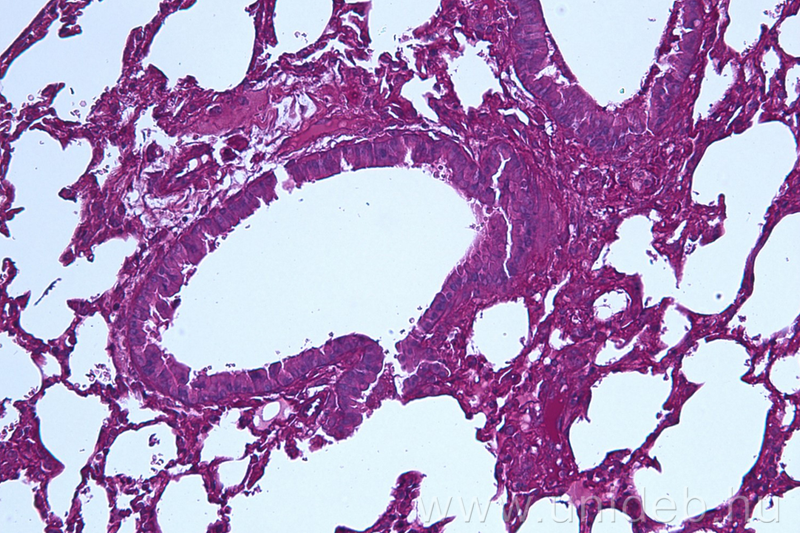

A Szentesi Péter által irányított tudóscsoport bebizonyította, hogy a PAF képes leküzdeni a tüdőben az Aspergillus gomba által okozott betegségét. Az egerekkel végzett tesztek során kiderült, hogy a PAF növelte az állatok túlélését és csökkentette a tüdejükben jelenlévő gomba mennyiségét.